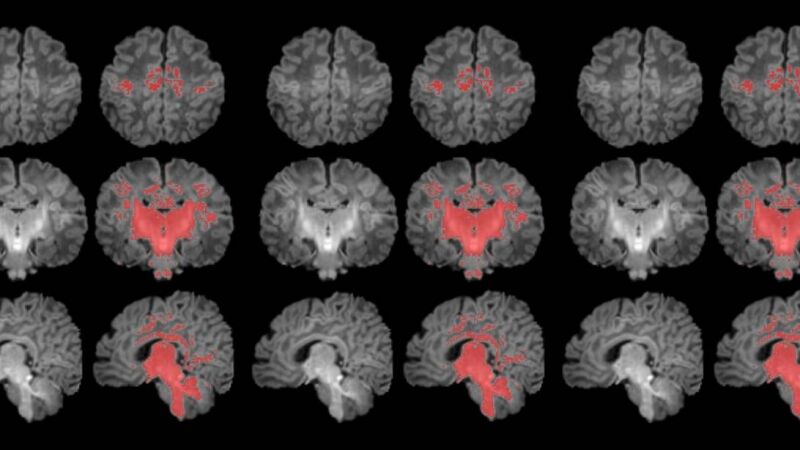

La exposición prenatal a la contaminación del aire se relaciona con una maduración más lenta del cerebro durante el primer mes de vida. Así lo ha revelado el primer estudio que mide con resonancia magnética la mielinización cerebral de los recién nacidos.

La mielinización es un proceso clave en la maduración del cerebro, en que la mielina recubre las conexiones neuronales y las hace eficientes para la transmisión de información. Los recién nacidos de madres expuestas a niveles más altos de partículas finas en suspensión durante el embarazo muestran una mielinización más lenta en esta etapa tan precoz de la vida.

Para llevar a cabo el estudio se reclutó a mujeres embarazadas en seguimiento en el Hospital Clínic Barcelona, el Hospital de Sant Pau y el Hospital Sant Joan de Déu. Se monitorizaron los niveles de contaminantes atmosféricos a los cuales estaban expuestos durante la gestación y, después del parto, se seleccionó a 132 recién nacidos. A estos se les realizó una resonancia magnética antes de cumplir el primer mes de vida para observar el grado de maduración cerebral según sus niveles de mielinización.

Los resultados muestran una correlación clara entre una mayor exposición materna a PM2.5 durante el embarazo y una menor mielinización en el cerebro de los recién nacidos.